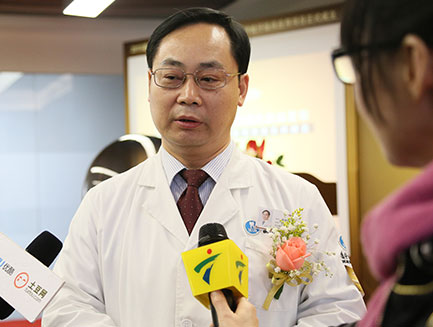

徐世同院长表示:

人们对种植牙成功的标准要求也越来越高。好的种植牙,一方面需要临床经验极高的医生,还需要先进设备的技术完美配合,才能做到完美。目前,较先进的舒眠数字化种植技术,是在全新一代德国数字化导板种植系统设备的前提下,增加将临床影像采集、口内或模型扫描取像、数字化舒眠技术;实现精准控制种植体的植入位置、方向和深度,避开关键性神经和血管,确保种植体安全植入,种牙时感到无恐惧,种植过程如同睡觉般舒适。